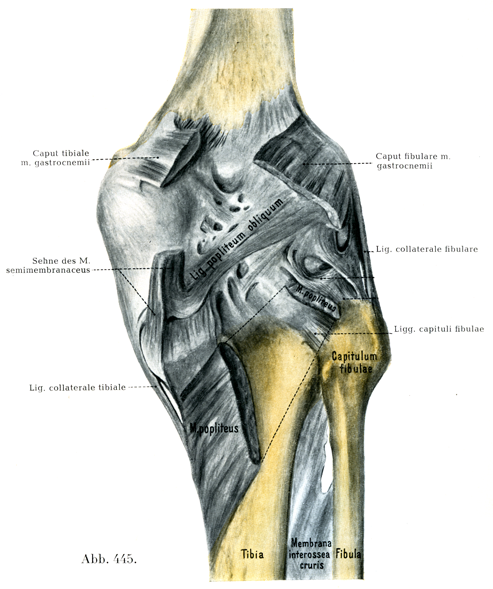

[図445]右の膝関節 後からみる(3/4)

6. 斜膝窩靱帯Lig. popliteum obliquumは半膜様筋の腱から放散する線維束の1つである.

8~15mmの幅で腓腹筋の腓側頭の起始に向って斜めに上外側へ走る(図445).

関節包の後面は両顆の上方で腓腹筋および足底筋の起始腱によって補強されている.特別の線維束としては次のものがある: